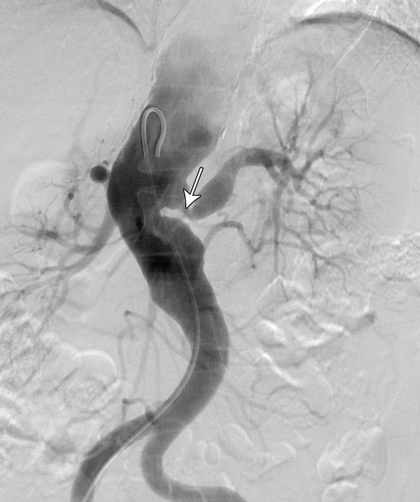

A computed tomography (CT) scan of the brain was unremarkable. Magnetic resonance imaging of the brain showed supratentorial T2-weighted and fluid-attenuated inversion recovery (FLAIR) white matter hyperintensity, suggesting moderate chronic small-vessel ischaemic disease. Carotid and vertebral duplex ultrasound confirmed high-grade stenosis in both internal and external carotid arteries. CT angiography showed extensive atherosclerosis for the patient's age and tight stenosis in the right internal carotid artery and distal aspect of the left common carotid artery. CT angiography of the thoracic aorta revealed a descending aortic aneurysm and thrombosis of the left subclavian artery. A CT renal angiogram revealed a stenosis at the origin of the left renal artery (Figure, arrow). A full body positron emission tomography scan could not be interpreted because of physiological uptake of contrast medium by brown fat, which limited the ability to evaluate for large-vessel vasculitis.